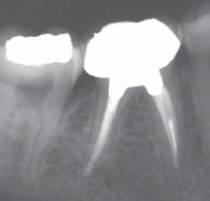

Снимок определения рабочей длины. Виден ByPass сломанного

инструмента.

Снимок наблюдения через 6

месяцев. Практически полное исчезновение периапикальных процессов на М и Д

корнях

4-в первую очередь, постараться напрямую обойти сломанный фрагмент, очень

аккуратно используя ручные инструменты. Зто техника называется «Ву Pass»

Процедура прохождение рядом со сломанным инструментом. Такая

процедура позволяет нам очистить канал апикальнее и тем самым решить проблему